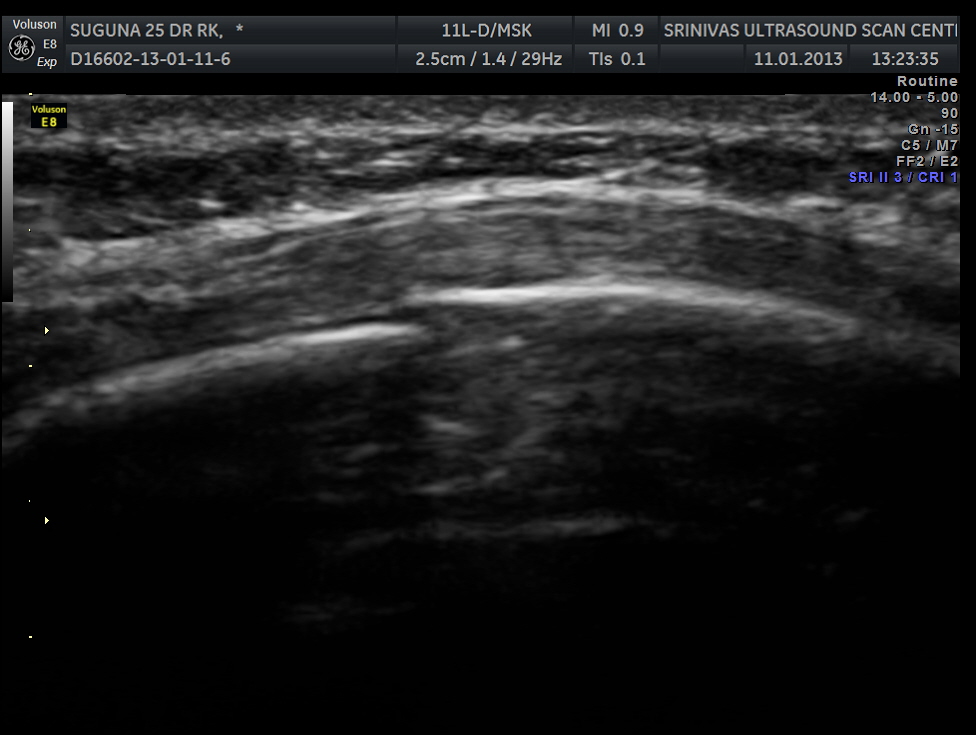

This was a 25 year old lady who fell on her chest while a cow was chasing her . She had persistent severe pain in the left side of the chest. Xray of the rib cage was reported as normal and appeared to be normal.

Scan over the point of maximal tenderness ( over the 6th rib on the left side anteriorly) revealed a crack in the bone on the posterior aspect . Probably as it was not a complete fracture it was missed on the xray.

The images are shown below